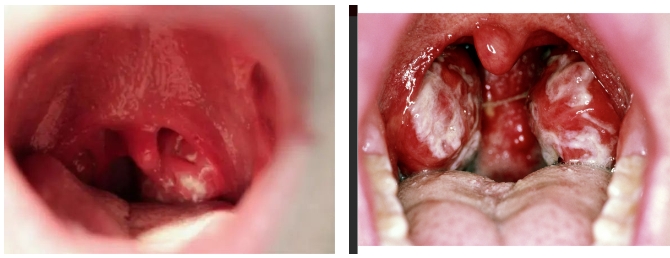

2.咽颊炎:

表现为咽痛,咽部、扁桃体,腭垂充血肿胀,扁桃体上有溃疡,被覆较厚的分泌物,严重的咽部水肿,引起吞咽困难及气道阻塞。